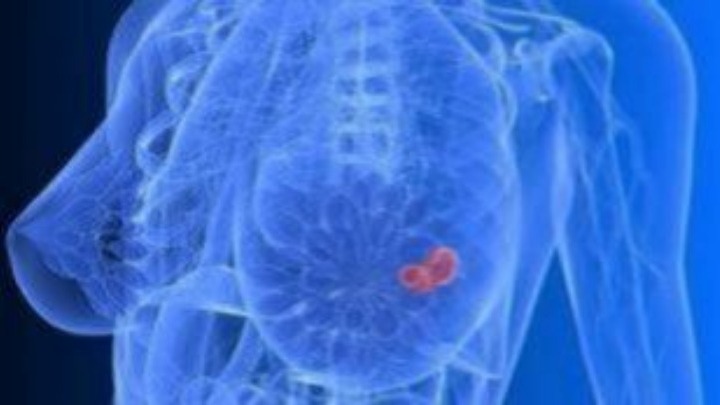

Αυξημένος ο κίνδυνος καρκίνου του μαστού για τις γυναίκες που κάνουν εξωσωματικές μετά τα 40

Οι γυναίκες μετά την ηλικία των 40 ετών που προσπαθούν να κάνουν παιδί με εξωσωματική γονιμοποίηση, κινδυνεύουν περισσότερο από καρκίνο του μαστού, σύμφωνα με μια νέα επιστημονική έρευνα.

Οι ερευνητές, που έκαναν σχετική ανακοίνωση στο ετήσιο συνέδριο της Ευρωπαϊκής Εταιρείας Ανθρώπινης Αναπαραγωγής και Εμβρυολογίας στη Βιέννη, ανέλυσαν στοιχεία για 58.534 γυναίκες που είχαν καταφύγει στην υποβοηθούμενη αναπαραγωγή. Διαπιστώθηκε ότι όσες είχαν γεννήσει με εξωσωματική μετά τα 40, είχαν κατά μέσο όρο 65% μεγαλύτερη πιθανότητα να διαγνωσθούν αργότερα με καρκίνο του μαστού.

Η θεραπεία της υπογονιμότητας ενεργοποιεί τις ωοθήκες, πράγμα που αυξάνει τα επίπεδα των οιστρογόνων στο σώμα της γυναίκας, με αποτέλεσμα να αυξάνεται η πιθανότητα ανάπτυξης καρκινικών κυττάρων στο μαστό. Πάντως, σύμφωνα με τη βρετανική «Ιντιπέντεντ», η πιθανότητα διάγνωσης με καρκίνο του μαστού είναι μικρή (περίπου 0,8%) για τις γυναίκες που γεννούν με εξωσωματική μετά τα 40.